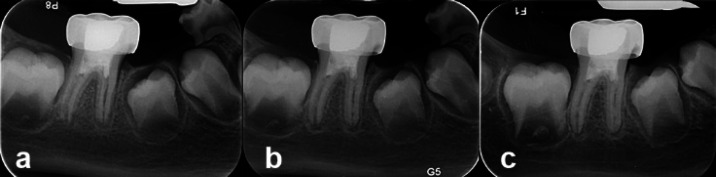

In this case report, the regeneration method was used to treat the previously treated first molar, which presented with symptoms of pain during chewing and secondary acute apical periodontitis. Due to the importance of preserving the patient's permanent teeth in order to maintain optimal space and function, the regeneration treatment was performed in two visits and according to the American Association of Endodontists (AAE) guidelines. The continuation of tooth root development, healing of periapical radiolucency and positive response to sensibility test (cold test) were observed during follow-up radiographs at intervals of 6 months, 1 year & 2 year.